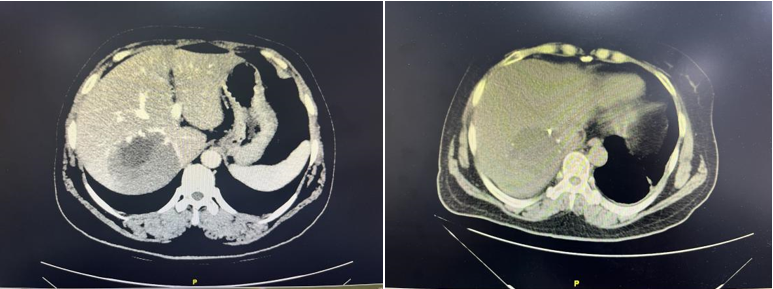

▲图2术前、术后复查CT对比提示肝脏恢复良好